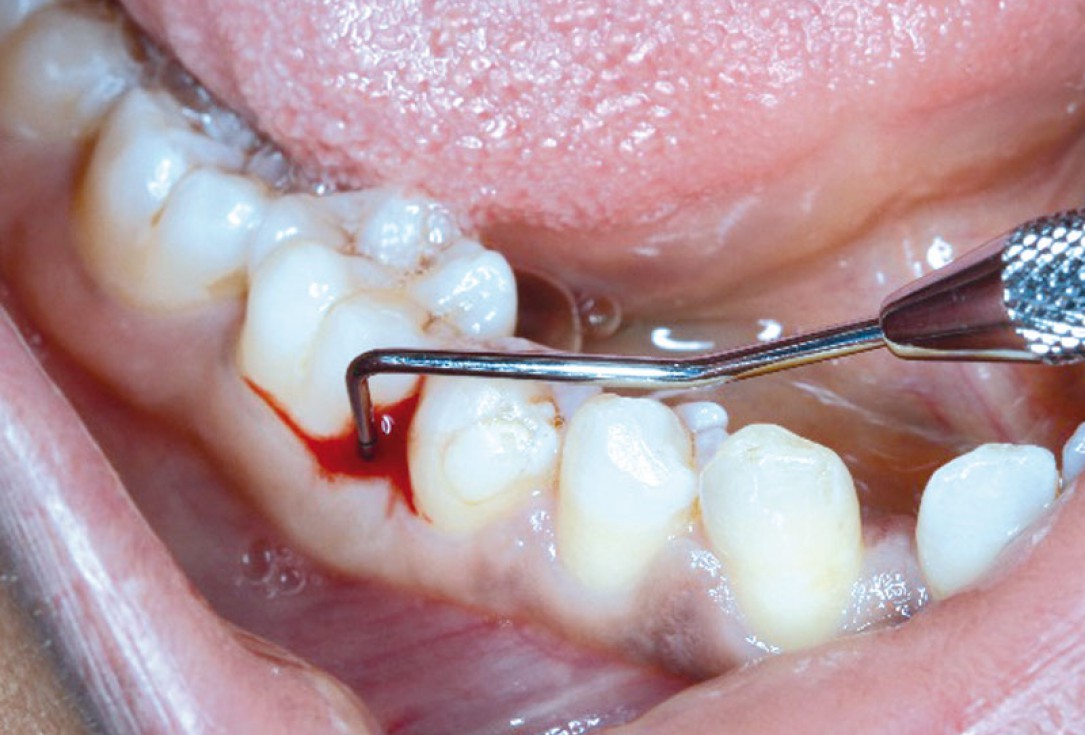

01/08 - PPD of 9mm at mesial of LR6Regeneration at LR6 with cerabone® and collprotect® membrane using simple papilla preservation technique - Dr. D. Chatzopoulou